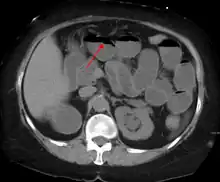

The main diagnostic tools are blood tests, X-rays of the abdomen, CT scanning, and ultrasound. If a mass is identified, biopsy may determine the nature of the mass.

Radiological signs of bowel obstruction include bowel distension and the presence of multiple (more than six) gas-fluid levels on supine and erect abdominal radiographs. Ultrasounds may be as useful as CT scanning to make the diagnosis.[17]

Contrast enema or small bowel series or CT scan can be used to define the level of obstruction, whether the obstruction is partial or complete, and to help define the cause of the obstruction. The appearance of water-soluble contrast in the cecum on an abdominal radiograph within 24 hours of it being given by mouth predicts resolution of an adhesive small bowel obstruction with sensitivity of 97% and specificity of 96%.[18]